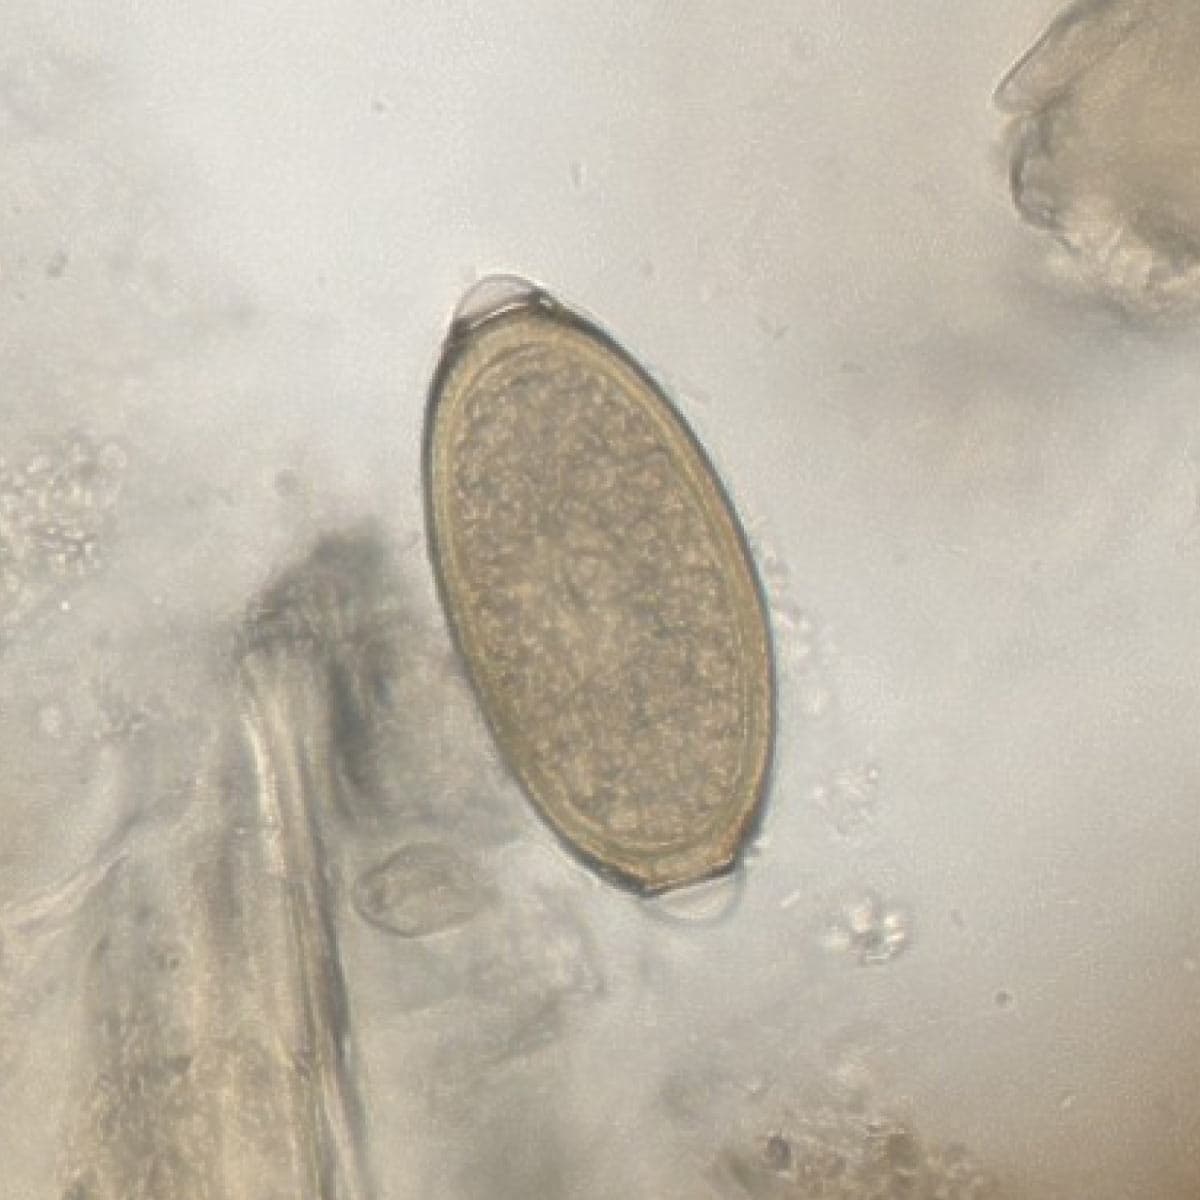

Automatic detection over 30 species

Built on worldwide parasite-positive specimens, ParaScout AI identifies a vast number of parasite species, including those that are clinically rare or challenging to find.